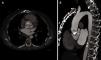

A los pocos meses, la paciente presentó clínica de insuficiencia cardiaca progresiva hasta ingresar en situación de anasarca. En la ecografía transtorácica (fig. 1 A y vídeo 1 del material adicional en anexo) y transesofágica (figura 1 B y vídeo 2 del material adicional en anexo) se observa fuga paraprotésica anterior (flecha) y amplio seudoaneurisma (asterisco) en la región posterior de la raíz aórtica (Ao), con flujo diastólico en su interior. También se observa la comunicación del seudoaneurisma, que presenta flujo de entrada supravalvular en raíz aórtica y de salida a ventrículo izquierdo, hallazgos que se comprueban posteriormente en la tomografía computarizada multidetector de 64 cortes (fig. 2 A y B) (fig. 3). Se realizó reparación quirúrgica con implante de homoinjerto criopreservado de raíz aórtica con buena evolución posterior.

El diagnóstico de las complicaciones valvulares posquirúrgicas resulta muchas veces complejo, por lo que cobra cada vez más importancia la imagen multimodal en cardiología. La combinación de las distintas técnicas de imagen resultó fundamental para el diagnóstico de un amplio seudoaneurisma aórtico fistulizante a ventrículo izquierdo, una complicación muy poco frecuente.